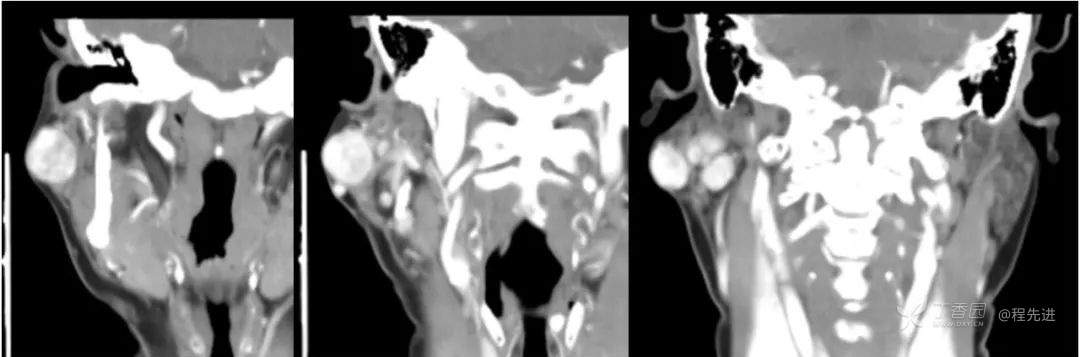

简要病史:发现右侧耳下肿物12年,不痛,缓慢生长

既往史:19年前因右侧腮腺肿物在当地医院行手术(具体不详),17年前因右侧腮腺肿物复发再次在当地医院手术(具体不详)

体格检查:右侧耳下可扪及大小约3*3cm肿物,质地中,边界清,活动可,无明显压痛。颈部未扪及明显肿大淋巴结